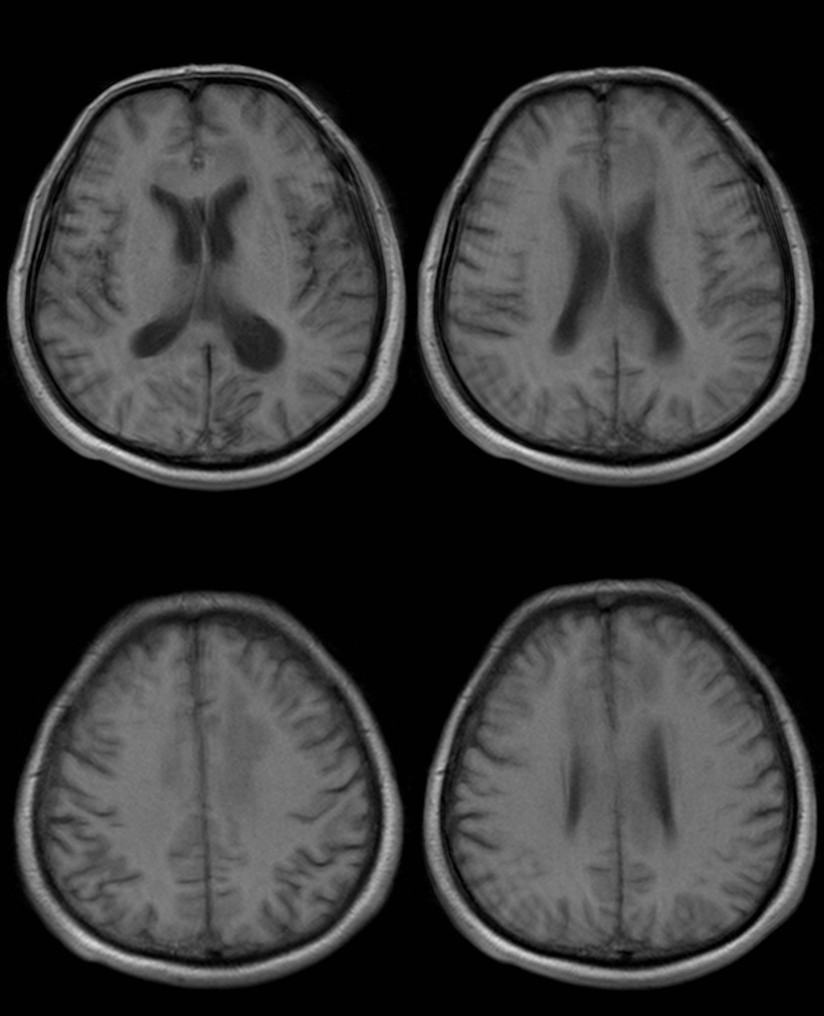

影像资料:

•急性期表现为胼胝体弥漫性肿胀,T1WI呈稍低信号,T2WI及FLAIR呈稍高信号,以矢状位观察最佳,可单独累及胼胝体压部或整个胼胝体,DWI呈高信号,ADC图呈低信号,部分患者可观察到脑室周围白质或内囊受累,少见皮层受累,表现为扩散受限,不强化和强化病例均可见到。如果增强扫描可见胼胝体有不同程度强化,呈小灶状或不规则斑片状,系血脑屏障破坏所致(如本例),本例患者处于急性期。

上排:原发性胼胝体变性急性期

下排:原发性胼胝体变性慢性期,表现为胼胝体萎缩、软化

急性期原发性胼胝体变性(胼胝体压部及体部病变,CT呈低密度,T1WI呈稍低信号,FLAIR呈稍高信号,扩散受限)向慢性期转变,慢性期胼胝体压部病灶出现坏死或囊变,FLAIR呈低信号